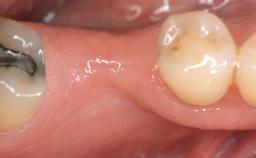

It is sometimes necessary to remove and replace compromised implants. This case is a clear example of the need for multiple steps to achieve an optimal therapeutic result for patients with non-salvageable implants. It illustrates how the lost soft and hard tissues were rebuilt in a sequence that improved the healing of the hard tissues and assured their long-term stability. The 35-year-old healthy patient presented with clinical attachment loss on the proximal and lingual surfaces of the natural dentition. Some gingival recession was present on natural teeth, particularly in the posterior sextants (S1, S3, S4, and S6).